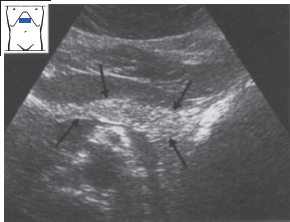

The normal pancreas is slightly less echogenic than the surrounding retroperitoneal fat (compare the pancreas with the fat around the SMA (above). Flow comes toward and then away from the transducer in a normal splenic vein. 1 case question available

Diagnosis of pancreatic diseases is based on increasing or decreasing echocardiography of the organ. If the organ is healthy, then normal echogenicity is observed. With increased parenchyma density or replacement of normal tissues with fat or connective, echogenicity increases. If echolineses of MI indicate a decrease in parenchyma, then this indicates inflammatory processes in the pancreas, acute or chronic pancreatitis. Depending on the severity and nature of diffusion, it is possible to diagnose not only pancreatitis, then diabetes mellitus, tumors, fibrosis and abscesses.

Why is the pancreas denser?